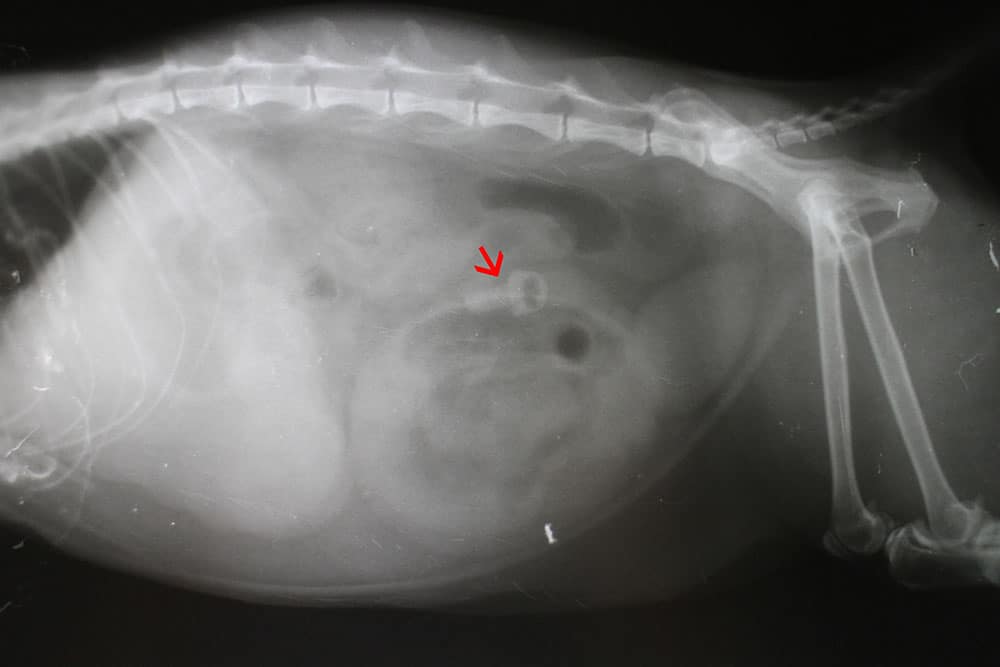

2. Digital radiography: identifies metallic or dense objects, gas accumulation patterns consistent with obstruction, and intestinal dilation

X-ray image of an animal’s abdomen, likely a cat or dog, with a red arrow pointing to a specific round opaque area, possibly indicating a foreign object or abnormality in the digestive tract.